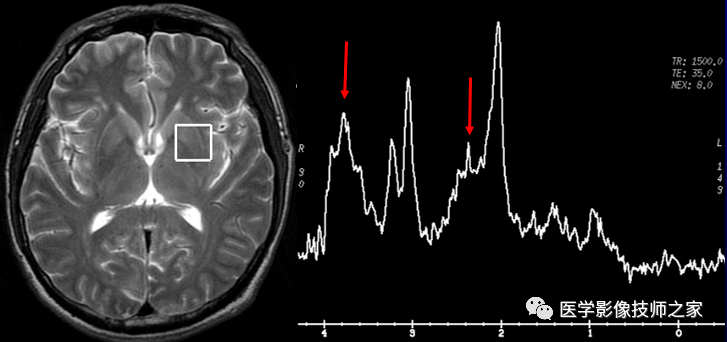

一文读懂!磁共振波普(mrs)检查